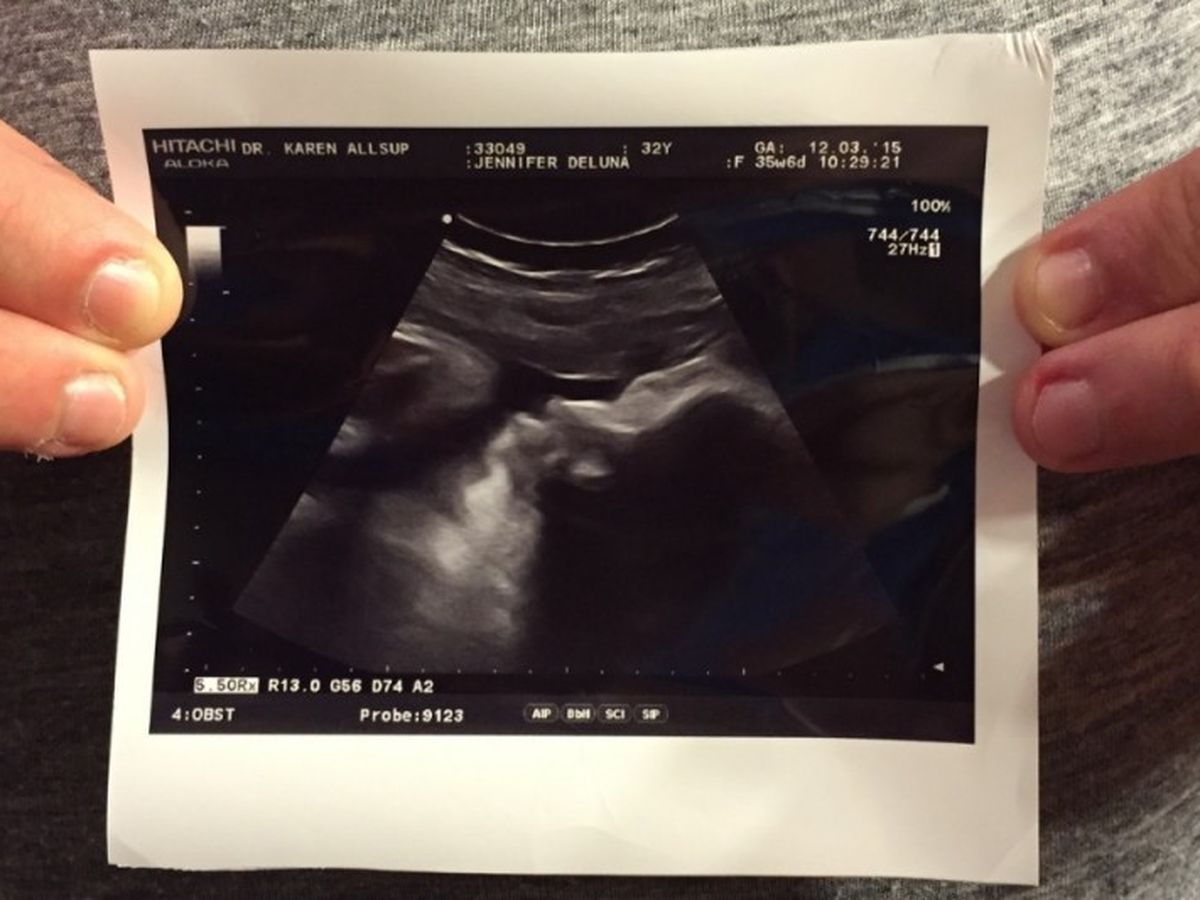

My name is Phillip Zavala and my beautiful other half, who is 8 1/2 months pregnant, is named Jennifer.

On Thursday, December 3, 2015, we went to a prenatal check up excited about the ultrasound where we would learn how much our unborn son, Noah, is now weighing. We left heart broken hearing that our unborn son only has two heart chambers. We were seen the next day by a perinatologist, a doctor specializing in high risk pregnancies. This specialist diagnosed our son as having hypoplastic left heart syndrome. He immediately referred us to a pediatric cardiologist where a fetal echocardiogram was done on our little Noah's heart. We were both in tears as now we had two doctors tell us our unborn son was going to have a tough battle ahead of him as he does in fact have a hypoplastic left heart.